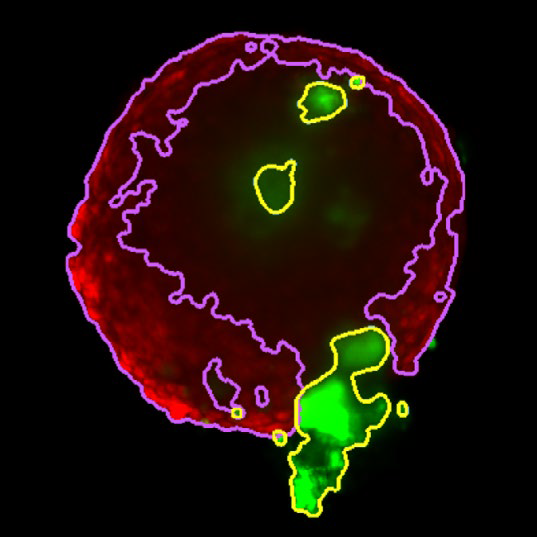

Figure 4. Z slice of the tumor microtissue treated with 5 μM Lapatinib - tumor (yellow region) is decreased significantly compared to the one treated with 0.005 % DMSO. Image Credit: Yokogawa Life Science

Tumor spheroids were created by seeding an Akura™ 384 plate with a monodispersed mixture of GFP-expressing NCI-N87 (gastric carcinoma) and RFP-expressing NIH3T3-L1 (murine fibroblast) cells, which spontaneously formed spheroids through scaffold-free self-assembly over several days. After spheroid formation, selected wells containing tumor spheroids were treated with DMSO at 0.05, 0.5, or 5.0 μM Lapatinib for six days. The images were analyzed in 3D, with NCI-N87-GFP (tumor) and NIH-RFP (fibroblast) identified separately, and the volume of each spheroid measured.

This research allowed InSphero AG to accurately quantify pharmacological effects on their 3D models. The fully automated system enhanced multi-condition simultaneous testing, leading to increased workflow efficiency. By implementing the HCA platform, InSphero AG provides seamless solutions, from in vitro 3D models to evaluations.